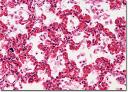

إن أهم بكتيريا تصيب الرئتين هي المكورات الرئوية (Streptococcus Pneumonia)

الالتهاب الرئوية بسبب الفطريات:

يتعرض المصابون بنقص المناعة للاصابة بـ التهاب الرئة الفطري ويكون الالتهاب الرئوي في هذه الحالة هو العلامة الاولى لمرض نقص المناعة، والفطر المسبب للمرض هو غالبآ (Pneumocystis Carinii)